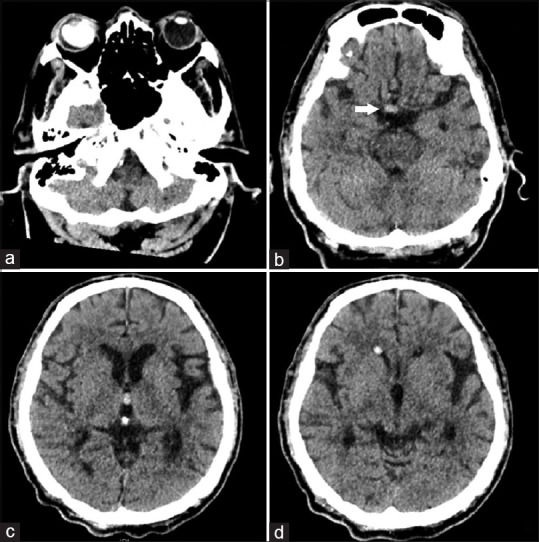

Intraventricular and subarachnoid migration of silicone oil from previous intraocular injection mimicking intracranial haemorrhage: a case report.